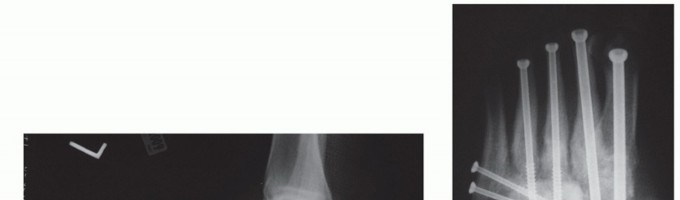

The two most common methods of internal fixation currently employed are large beaming intramedullary screws or rigid medial plate and screw constructs (FIG 7).22,25

--- FIG 7 • A,B. Preoperative weight-bearing radiographs on a 57-year-old diabetic female with no open wounds. She underwent correction of the deformity followed by internal fixation with super construct beaming screws.

FIG 7 • (continued) C,D. Radiographs at 1 year, demonstrating successful union.*

Internal fixation can be achieved with either intramedullary screws or a large medial screw-plate construct.

Beaming is accomplished by passing large intramedullary screws from the metatarsophalangeal joints of the first and fourth metatarsals across the osteotomy and into the talus. This superstructure concept theoretically behaves much like an intramedullary nail.

Several device manufacturers have developed large medial plates that can be used with “osteoporosis” large threaded screws to optimize stabilization in this patient population with poor bone quality.22,25 -